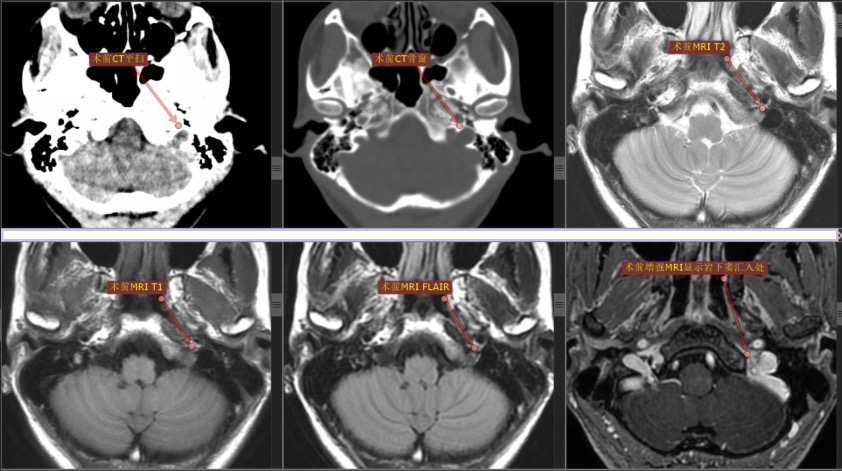

手术采用左侧远外侧入路,使用纯内镜手术,内镜采用国产德龙4K纯高清内镜摄像系统,发现左侧第Ⅸ、第Ⅹ和第Ⅺ颅神经穿过颈静脉孔处肿瘤。

术中显示肿瘤质地较硬,直径约1cm,包绕左侧第Ⅸ、第Ⅹ和第Ⅺ颅神经并与硬脑膜粘连紧密。使用精细磨钻磨除颈静脉孔区部分骨质,充分暴露肿瘤。在电生理监测和德龙4K超高清内镜系统显示下完全切除肿瘤,保留神经,未出现大出血。